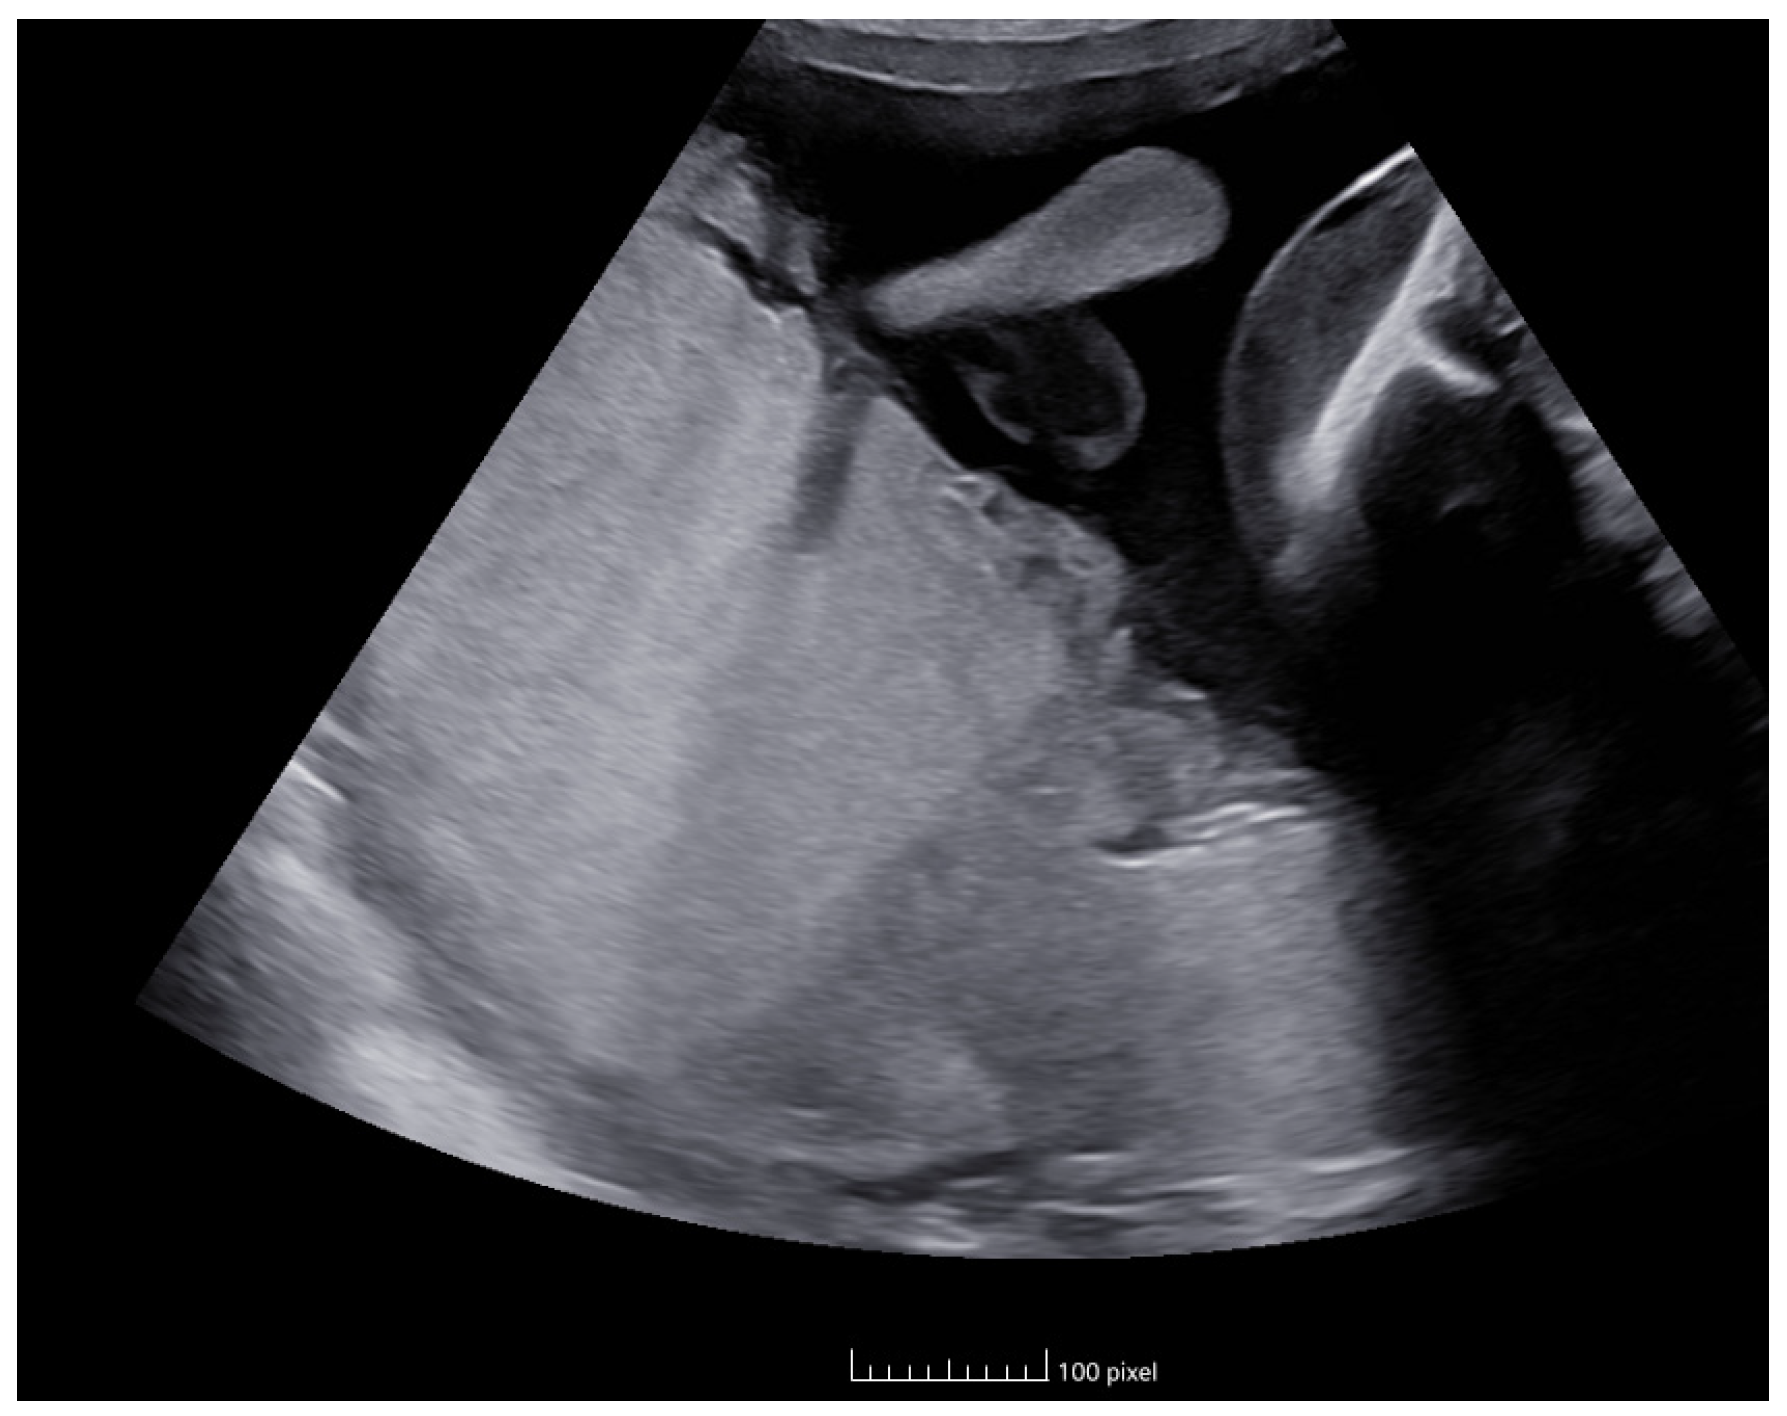

In Figure 2, we can observe the evolution of both the PSV and the delta value during subsequent follow-up assessments.

Figure 2. Evolution of PSV and delta value.

Following the ultrasound values observed at week 31 + 2 (02/27), the first fetus had an MCA-PSV of 24 cm/s (0.55 MoM) with no signs of cardiac compromise, and the second fetus had an MCA-PSV of 70 cm/s (1.7 MoM) with no signs of cardiac compromise, with a delta MCA-PSV value of 1.1 (Stage II).

Due to the progression of the pathology in the last ultrasound check (Figure 3), the case was presented to the obstetric committee, where intrauterine fetal transfusion was dismissed due to the risk of fetal damage during the procedure and the great technical difficulty of accessing the anemic fetus. For this reason, the case was considered as a progressive Stage II, and after ruling out the possibility of intrauterine transfusion, it was decided to schedule an elective cesarean section at 32 weeks for fetal interest, with the first twin in a breech presentation after completing neuroprotection with magnesium sulfate.

Figure 3. Doppler ultrasonography of evolution of MCA-PSV of the twins.